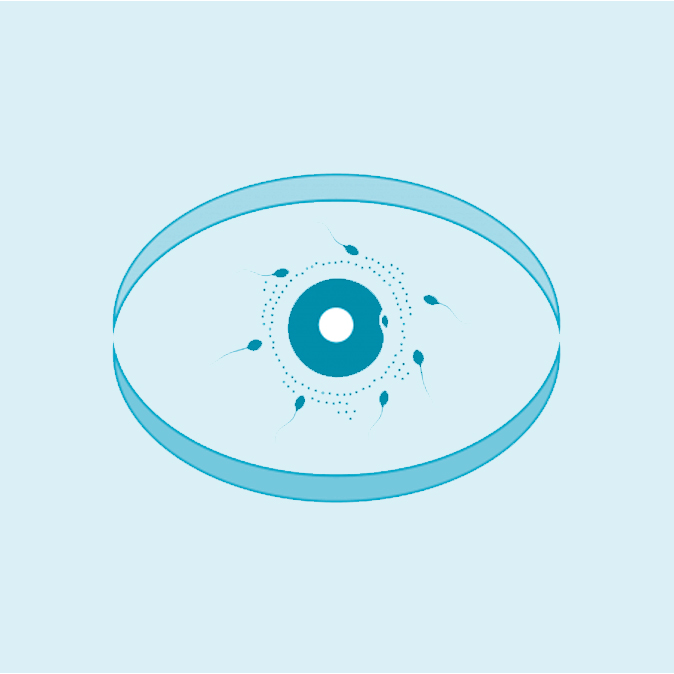

Fécondation in Vitro

La référence

Nous mettons à la disposition de nos patients un bloc opératoire hautement équipé, dédié aux interventions de fertilité et aux techniques innovantes de chirurgie mini-invasive, garantissant précision, confort et récupération rapide. Notre laboratoire de biologie de la reproduction, doté d’équipements de pointe, assure toutes les étapes essentielles : fécondation in vitro (FIV), ICSI, congélation d’ovocytes et d’embryons, diagnostic embryonnaire, optimisation de la qualité ovocytaire et spermatique… Chaque procédure est réalisée selon les standards internationaux afin d’assurer les meilleures chances de réussite.